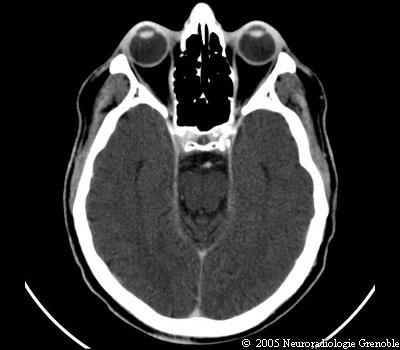

Radioanatomie TDM de l'encéphale

TDM cérébrale sans injection